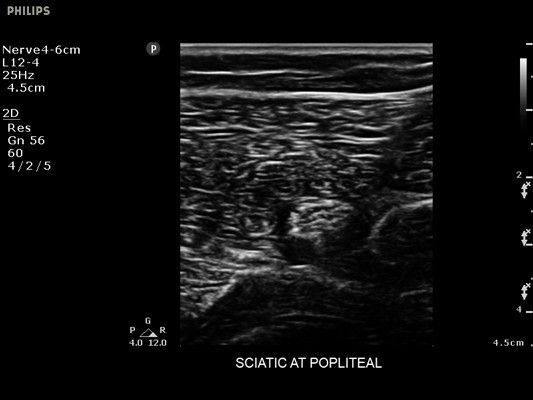

• Усиленная визуализация иглы без потери качества изображения окружающих тканей

• Диагностика нервов

• Линейный УЗИ датчик Philips L12-4